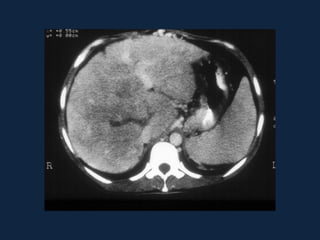

ESTEATOSE HEPÁTICA

ACENTUADA

• Ocorre uma diminuição na eficácia da TC de

identificar lesões focais hepáticas.

• Pode ocorrer uma inversão no padrão visual das

lesões focais, em relação às comparações usuais de

atenuação feitas com o fígado normal.